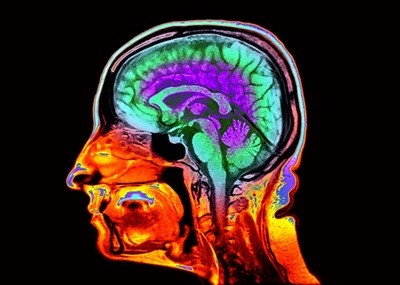

In their study, Kuceyeski and her colleagues set out to investigate sex-linked variation in brain development by analysing functional magnetic resonance imaging brain data from 1,286 people, half of whom were male and half female. The scans captured a snapshot of each individual’s brain age, but did not follow the same people throughout their lives. The analysis was based on sex at birth because the researchers didn’t have data on the participants’ gender identities.

They used an artificial-intelligence tool they call Krakencoder to identify sex-linked differences in brain networks. The tool analysed structural connections — physical axonal links between brain regions — and functional connections, which included synchronized brain activity between brain regions.

Their analysis revealed sex-linked differences in both structural and functional pathways in the brain. Functional differences were mainly in higher-order brain networks, which use information from many brain regions to support attention, decision-making and consciousness. Structural differences peaked in midlife and continued to diverge with age, particularly in lower-order networks, which process information gleaned by the senses.

Throughout life, female participants tended to have stronger functional connections than did male participants between ‘default mode network’ regions, which deal with higher-order processes. And as men got older, their functional connections between the two hemispheres of the cerebellum, used in motor control, grew increasingly strong compared with those of women. Structural connections on each side of the cerebellum also grew stronger in male participants than female participants as they aged.